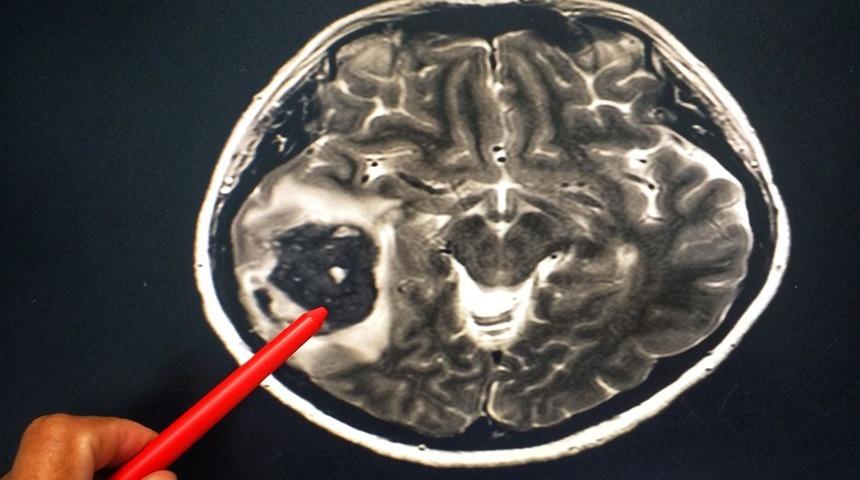

Araştırmacılar, çalışmada verileri incelenen vakalara, zihinsel durumları değiştiği, konuşma veya görme güçlüğü gibi nörolojik problemleri olduğu için MRI taraması yaptıklarını belirtti. Beyin taramasısının ardından 18 hastanın durumunun kritik olduğunun ortaya çıktığı, daha sonra bu hastaların beyne giden kan damarlarıın tıkalı olması nedeniyle bayin kanaması ya da felç geçirdiği belirtildi. Ardından 3 kişinin beyin kanamasını nedeniyle yaşamanı yitirdiği aktarıldı.

Öte yandan araştırmacılar, en kötü beyin taraması sonuçlarına sahip olanların kanlarında daha yüksek iltihap seviyesinin görüldüğünü bildirdi. Ağır Covid-19 hastalarının çoğunda virüs damarları daraltarak kan akışının yavaşlamasına ve pıhtılaşmaya neden oluyor.